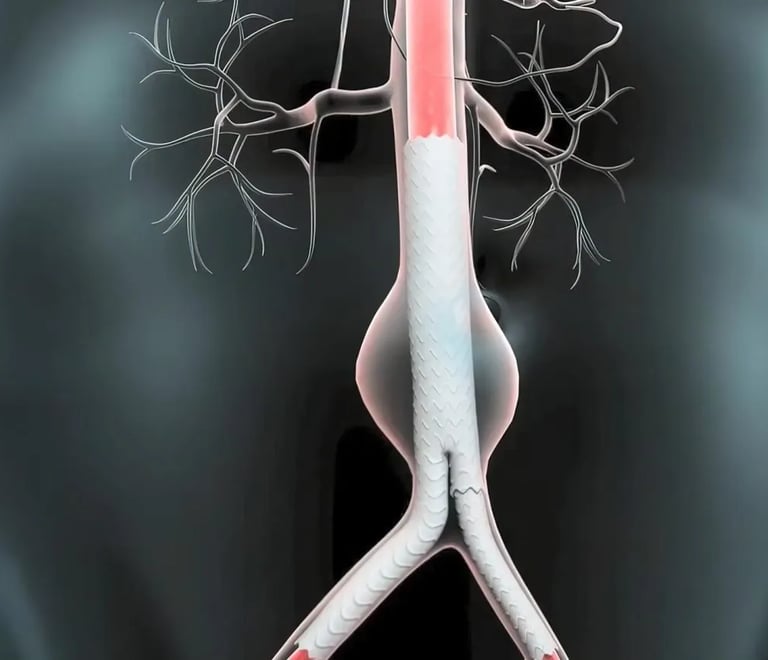

Aortic & Structural Heart Diseases

From aortic aneurysm evaluation to structural heart interventions, Dr. Anil’s expertise ensures early detection and minimally invasive treatment using the latest imaging and device technologies.